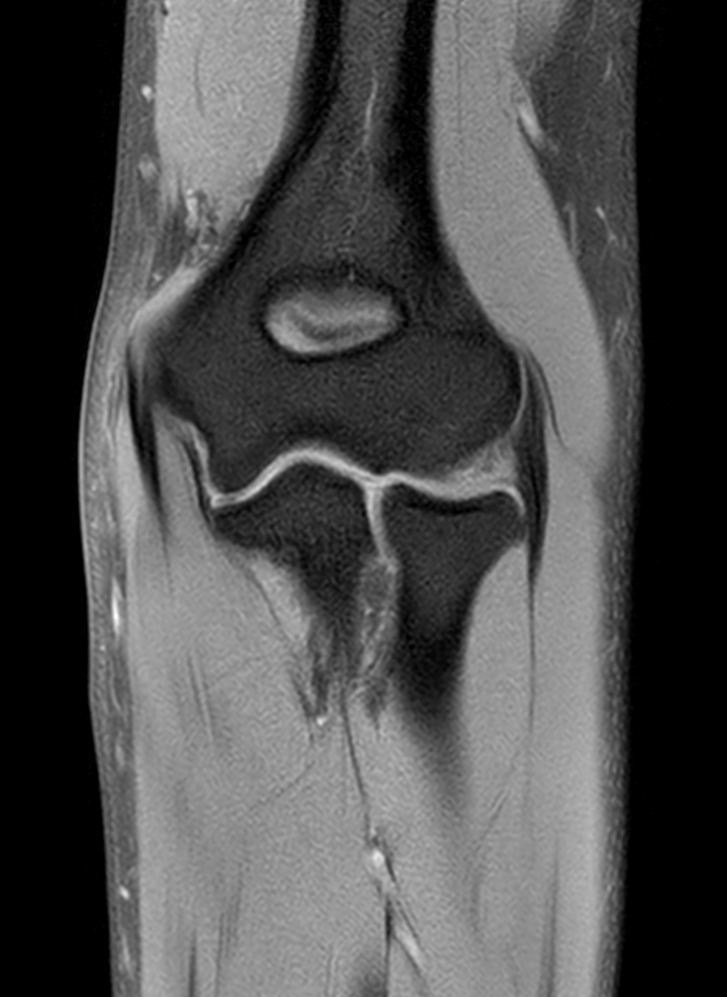

High quality Elbow imaging with Compressed SENSE

Spital Uster, Switzerland